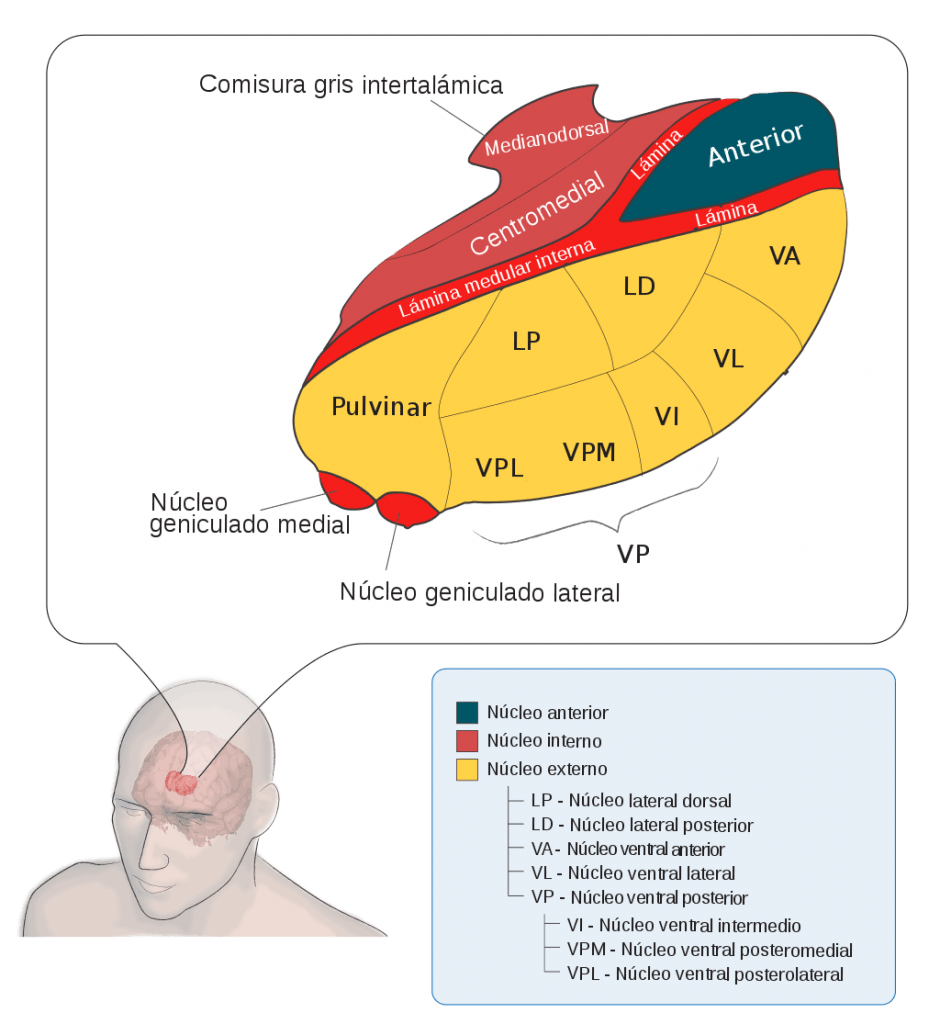

És la regió més gran del diencèfal (80% del total) i està constituït per masses parelles i ovalades de substància gris, que es disposen com nuclis entre fascicles de substància blanca i estan situades a ambdós costats del tercer ventricle, formant 4 cares.

Tenint en compte la seva posició i les seves funcions, trobem 7 grups principals de nuclis a cada costat del tàlem:

- Nucli anterior – Actua en les emocions, la regulació de l’estat d’alerta i la memòria

- Nuclis medials – Participen en les emocions, l’aprenentatge, la memòria, el grau de consciència i la cognició (pensament i coneixement)

- Nuclis del grup lateral – Actuen en l’expressió de les emocions i en la integració de la informació sensitiva

- Nuclis del grup ventral – Contribueixen a les funcions motores (planificació del moviment), a la transmissió d’impuls de sensacions somàtiques com el tacte, la pressió, la propiorecepció la vibració, el calor, el fred i el dolor

- Nuclis intralaminars – Participen en la percepció del dolor, la integració d’informació motora i sensitiva i en el despertar

- Nucli de la línia mitja – Es creu que actua en la memòria i l’olfacte

- Nucli reticular – Integra i filtra les activitats dels altres dos nuclis talàmics